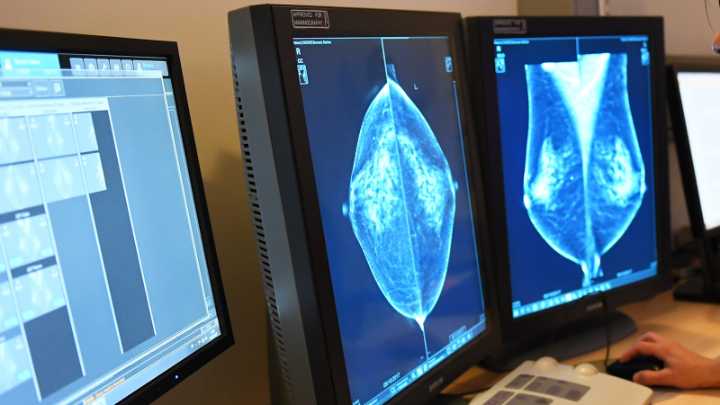

Modelos 3D que hacen visible lo invisible. Investigadores del Instituto Politécnico Nacional (IPN) de México desarrollaron una técnica que utiliza la impresión en 3D de la estructura interna de las mamas para detectar posibles tumores, planear cirugías y enseñar a nuevas generaciones de médicos.

Así puede ayudar la impresión 3D a detectar el cáncer de mama